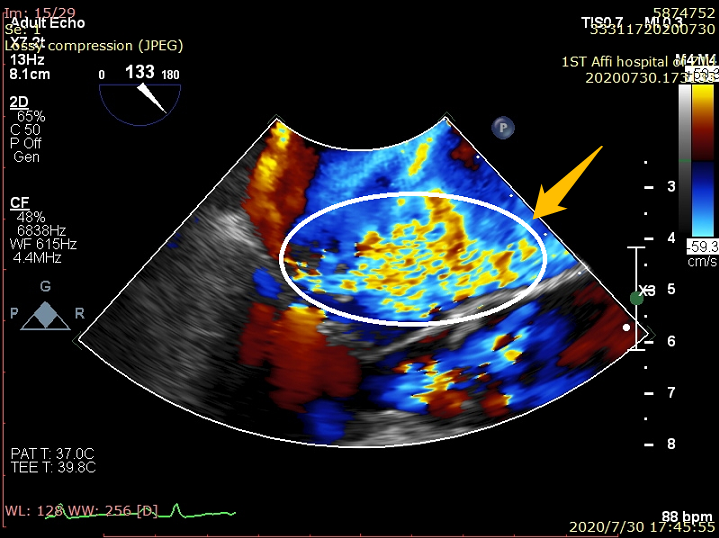

该例患者为73岁男性患者,主因“活动后气促十余年,加重二十余天”入院,诊断为重度二尖瓣关闭不全。患者的超声心动图提示二尖瓣后叶脱垂、腱索断裂并伴有重度二尖瓣反流(4+)。经过多学科团队的全面评估和反复讨论论证,马量主任、李伟栋主任及其团队认为该患者外科开胸心脏手术风险大,经心尖MitralStitch®微创二尖瓣修复手术是该患者的最佳治疗方式。手术在患者全麻状态下进行,术中于患者肋间行3-4cm小切口,经心尖穿刺送入器械,于二尖瓣A2区和P2区分别植入人工腱索完成缘对缘修复,并于P1区完成人工腱索植入,术后即刻二尖瓣反流量由重度(4+)变为无反流(0),二尖瓣瓣膜功能即刻恢复正常。手术操作在单纯超声引导下进行,手术过程平稳顺利,仅耗时25分钟。患者术后康复顺利,第2天便可自己下床活动,出院前复查超声心动图显示二尖瓣反流量为(0+),手术效果极佳。此次手术的成功标志着MitralStitch®确证性临床研究在浙大一院正式开展。

术前:大量彩色反流